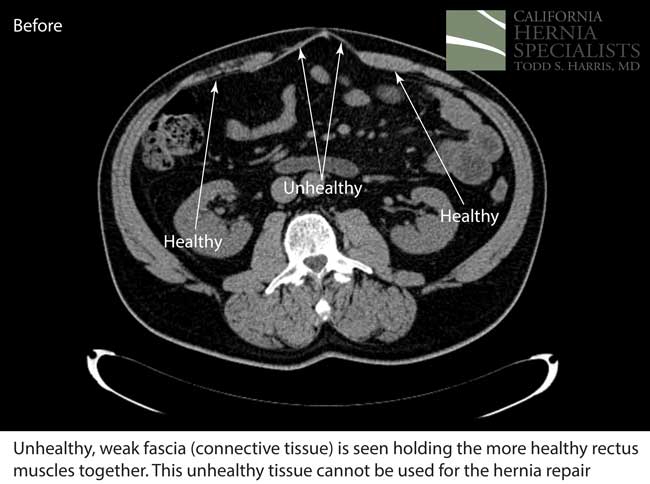

This initial CAT scan image shows why the hernia repair continued to fail. There is very weakened muscle in the middle of the abdomen with most of the healthy muscle several inches away on each side. More likely than not, the prior surgeon simply sewed the meshes into this unhealthy layer of fascia instead of bringing together the normal, healthy muscle.